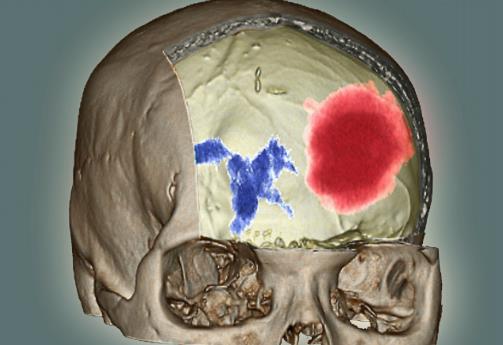

在了解腦出血的前兆之前我們先要看看什么是腦出血。腦溢血又稱腦出血、發病急且進展迅速。數據顯示在發生腦出血的患者中50%有先兆癥狀。腦溢血是指腦內微血管破裂出血是老年人的常見病好發于寒冷的冬季。常常表現為突然的一側肢體麻木、無力或癱瘓,因此病人會在毫無防備的情況下跌倒或手中的物品突然掉地同時伴有口角歪斜、流口水、語言含糊不清或失語,嚴重者伴有意識障礙、大小便失禁等。病因多與高血壓、動脈硬化有關具有起病急、后遺癥多等特點對老人的危害很大是中老年人致死性疾病之一。